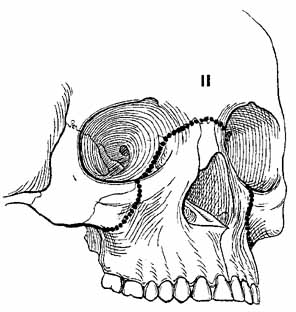

Complex orbital fractures include LeFort, naso–orbital–ethmoidal, zygomatic–maxillary–complex (ZMC or trimalar) and rim fractures. Generally, these fractures are repaired with a multidisciplinary approach provided by plastic surgeons, otolaryngologists, or maxillofacial surgeons. Fractures of the zygoma usually produce a ZMC fracture at three articulation sites: the frontozygomatic suture, the zygomaticotemporal suture, and the zygomaticomaxillary suture. The fracture may cause palpable step-offs of the orbital rim, flattening of the malar eminence, inferior displacement of the lateral canthus, and enophthalmos. The LeFort I (Guerin's) fracture occurs horizontally across the maxilla at the base of the nasal septum, is caused by trauma to the lower midface, results in malocclusion, and does not involve the orbit. The LeFort II (pyramidal) fracture extends from the nasofrontal suture along the nasal bridge to the medial wall at the level of the cribriform plate, posteriorly onto the orbital floor, and through the maxillary sinus (Fig. 14). This fracture results from trauma to the anterior mid-face, which causes a disarticulation of the body of the maxilla and mid-face from the zygomatic arch and cranium. In these injuries, the mid-face often has a sunk-in appearance.61 Epistaxis is a common associated finding. The more ominous cerebrospinal fluid rhinorrhea also occurs frequently, and it requires consultation of a neurosurgeon. A palpable inferior orbital rim step-off may be associated with infraorbital hypesthesia. Optic nerve trauma must be suspected. The globe may be enophthalmic and vertically displaced, and it may demonstrate extraocular motility disturbances.

Fig. 14 LeFort II fracture. (From Iliff NT: The ophthalmic implications of the correction of late enophthalmos following severe midfacial trauma. Trans Am Ophthalmol Soc 89:477–548, 1991)

The LeFort III fracture (craniofacial dysjunction) is a disarticulation of the facial skeleton from the base of the skull (Fig. 15). The fracture extends from the nasofrontal suture to the medial orbital wall at the level of the cribriform plate, along the orbital floor, following the inferior border of the greater wing of the sphenoid, and across the lateral wall, through the zygomatic arch and pterygoid plates. Because of the more posterior extent of this fracture, structures in the optic foramen and superior orbital fissure are highly susceptible to injury.

Fig. 15 LeFort III fracture. (From Iliff NT: The ophthalmic implications of the correction of late enophthalmos following severe midfacial trauma. Trans Am Ophthalmol Soc 89:477–548, 1991)